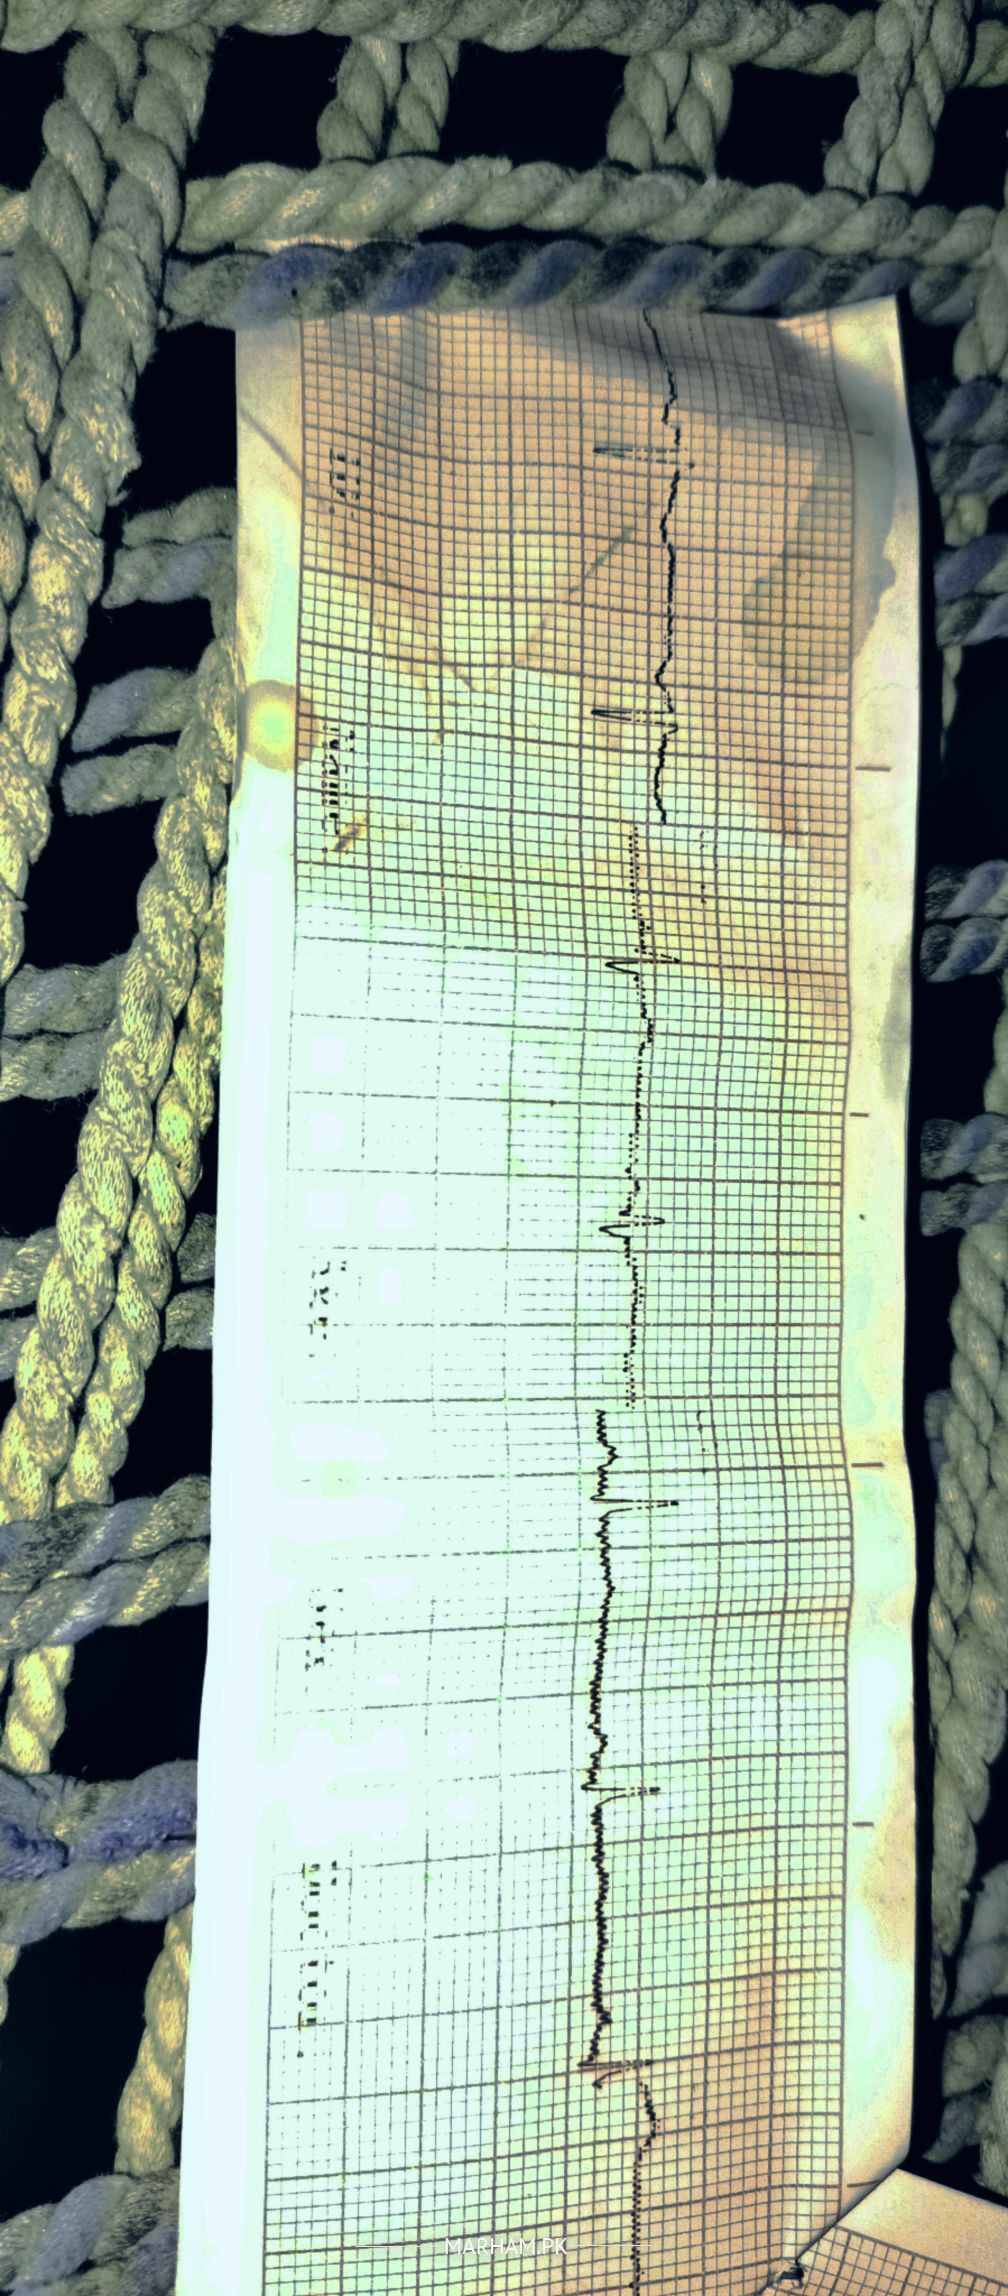

Talk to Cardiologist on Ecg

Asking For Self, Male 24, hyderabad

please check my attached ecg

kindly reason the ful strip of ecg,

this ecg strip is half but looks normal..

please send a better and full picture